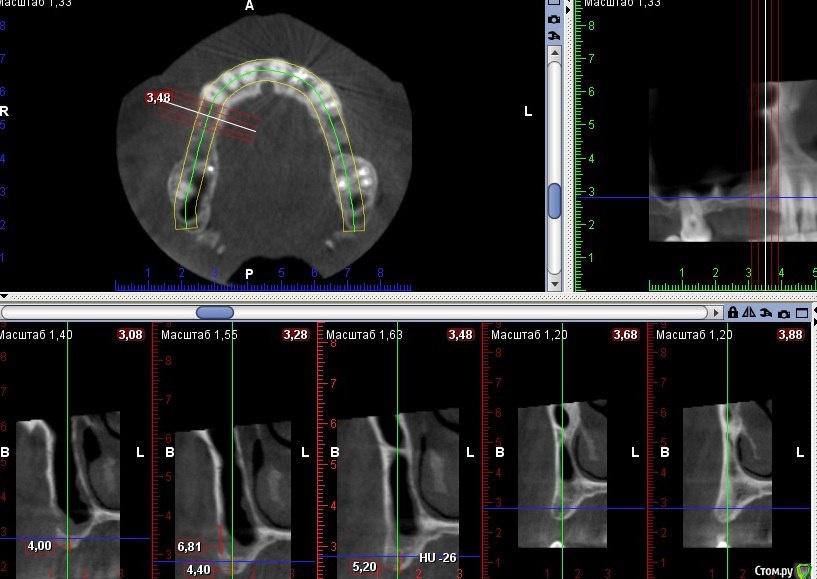

Kovalov Igor Опубликовано 19 мая, 2016 Поделиться Опубликовано 19 мая, 2016 (изменено) Здравствуйте уважаемые форумчане! Нужен совет по повторному синуслифтингу....3 месяца назад проводилась попытка синуслифтинга в 1 сегменте, отсутствие 14,15,16 зубов ... Разрез, формирование окна, в этом случае выбрал вход в синус с двух окон в проекции 14 и 16, получить перфу возле септы в области 16 когда отслаивал ... 14 отслойка без проблем... закрыл окна мембраной и ушил отправил погулять на 2,5-3 месяца.Вопрос как поступить ? Сделать одно большое окно? Как быть со спайками и как сложно их отделять ? Мембрану под перфу не подложил так как не делал ниразу этого... Кт после 3х месяцев ... Изменено 19 мая, 2016 пользователем Kovalov Igor Ссылка на комментарий

kriokov Опубликовано 19 мая, 2016 Поделиться Опубликовано 19 мая, 2016 пошел бы стандартно одним окном, да и первый раз думаю надо было одним окном идти, там не полная септа.Иногда приходиться остро работать на спайках как при расщеплении. Не знаю, но мне здесь одно здоровое окно видиться. И наверное зря Вы септу не спилили или не выкусили при первом заходе, если решили через три мес на повторный идти. Синус не плохо выглядит, думаю нормально все будет. 6 Ссылка на комментарий

kriokov Опубликовано 20 мая, 2016 Поделиться Опубликовано 20 мая, 2016 1 грамма мало на такой синус' даже крупного. 1,5 - 2 гр думаю 4 Ссылка на комментарий

red_butler Опубликовано 21 мая, 2016 Поделиться Опубликовано 21 мая, 2016 Куда вы 2гр L сыпите та? Тромбуете штоль?Даже еще раз пересмотрел срезы, Вы считаете что на такой операционной площади и при таком строении синуса расход будет меньше? 3 Ссылка на комментарий

Kovalov Igor Опубликовано 21 мая, 2016 Автор Поделиться Опубликовано 21 мая, 2016 Даже еще раз пересмотрел срезы, Вы считаете что на такой операционной площади и при таком строении синуса расход будет меньше?Ушло 2 грамма вы правы! ))) Спасибо всем за советы , ошибки были в первом случае малое и высоко расположенное окно, сделал в этот раз одно большое окно, спайки были только по периметру окна , было ощущение что окно начало заростать костью через три месяца, будто пластинка была поверх мембраны , может показалось ...Отслаивал до септы, графт 1,5 гр. в синус и 0,5 латерально от винтов и укрыл мембраной 25*25 владмива, мембрана не понравилась если честно ) Ссылка на комментарий